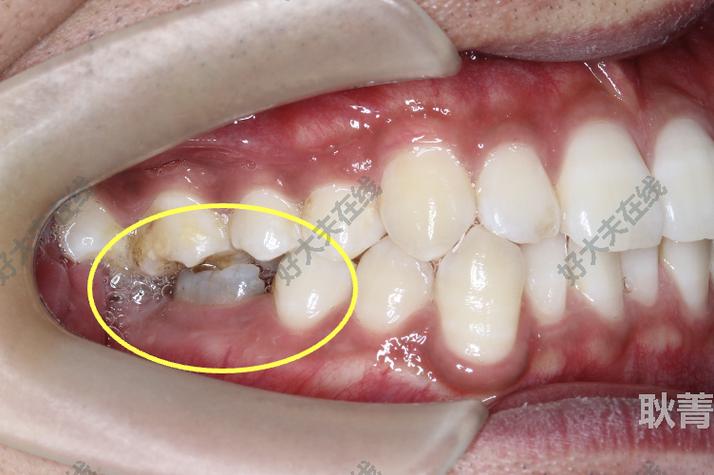

- 病例评估:通过X线片(曲面断层片、根尖片)、模型分析、口内检查明确间隙大小、牙齿位置、牙根形态及骨密度,判断是否适合滑动法(如牙根无明显弯曲、骨量充足者更佳)。

- 托槽粘接:精确粘接托槽,确保托槽槽沟与牙齿长轴平行,尤其移动牙的托槽位置需精准,否则会导致牙齿倾斜或扭转。

- 口腔卫生维护:正畸期间食物残易堆积托槽周围,需指导患者使用正畸牙刷、牙线、冲牙器清洁,避免牙龈炎、龋坏。

- 定期影像学检查:每3个月拍摄根尖片观察牙根吸收情况,若牙根吸收超过根长1/3,需暂停加力并调整治疗方案。